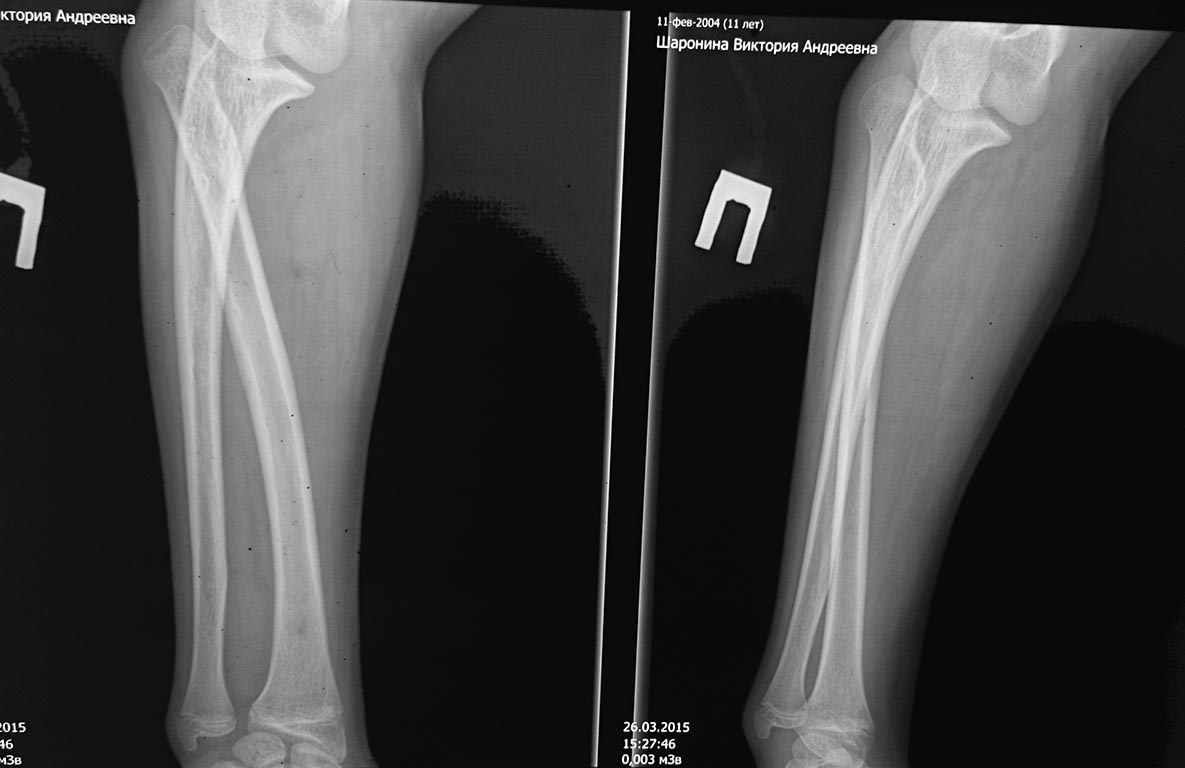

Помогите с тактикой лечения. Обратился подросток, девочка 14 лет. На

снимках вывих головки луча. Давность, со слов, матери с раннего детства.

Имеется парез глубокой ветви лучевого нерва-кисть и пальцы не разгибает.

Супинация резко ограничена по сравнению со здоровой

рукой. кисть правая, правша. Нужно ли оперировать и как? Как варианты

рассматриваем резекцию головки, транспозиция сухожилий, клиновидную

резекцию на уровне шейки луча и синтез минипластиной. Рентген прилагаю с

контролем здоровой руки.